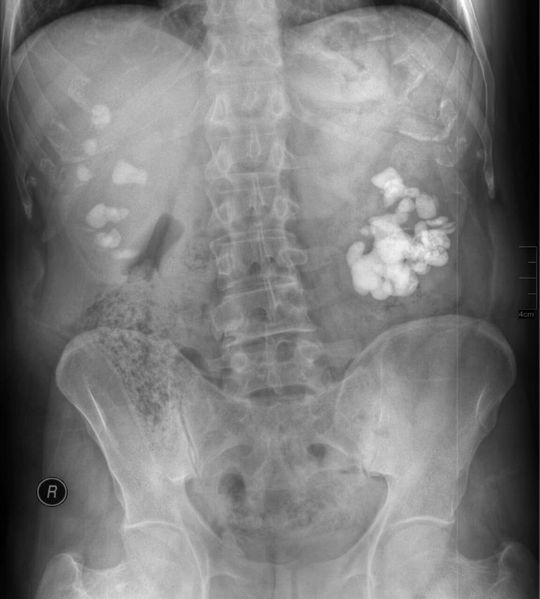

Staghorn calculus on the left & multiple renal stones on the right